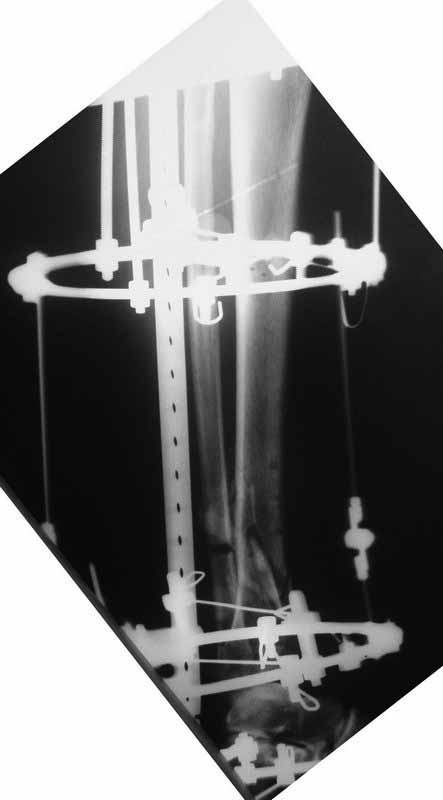

Это гипотрофический ложный сустав. Проблем видится несколько:

1. нарушение трофики в месте перелома.

2. после фиксации в аппарате Илизарова на рентгеногнрамме имеются признаки спицевого остеомиелила. В настоящи момент хотя свищей нет с мая 2011 нет опасно ли фиксировать голень стержнем?

На основании каких признаков Вы решили, что кость мертвая! Имеется гиперпластический ложный сустав, как результат недостаточно стабильной фиксации ан предыдущих этапах лечения. В данном случае необходимо решение следующих вопросов:

1 наличие инфекция в зоне ложного сустава

2. коррекция оси

3. окончательная стабильная фиксация

4. исключение предыдущих ошибок

5. оценка своих возможностей.